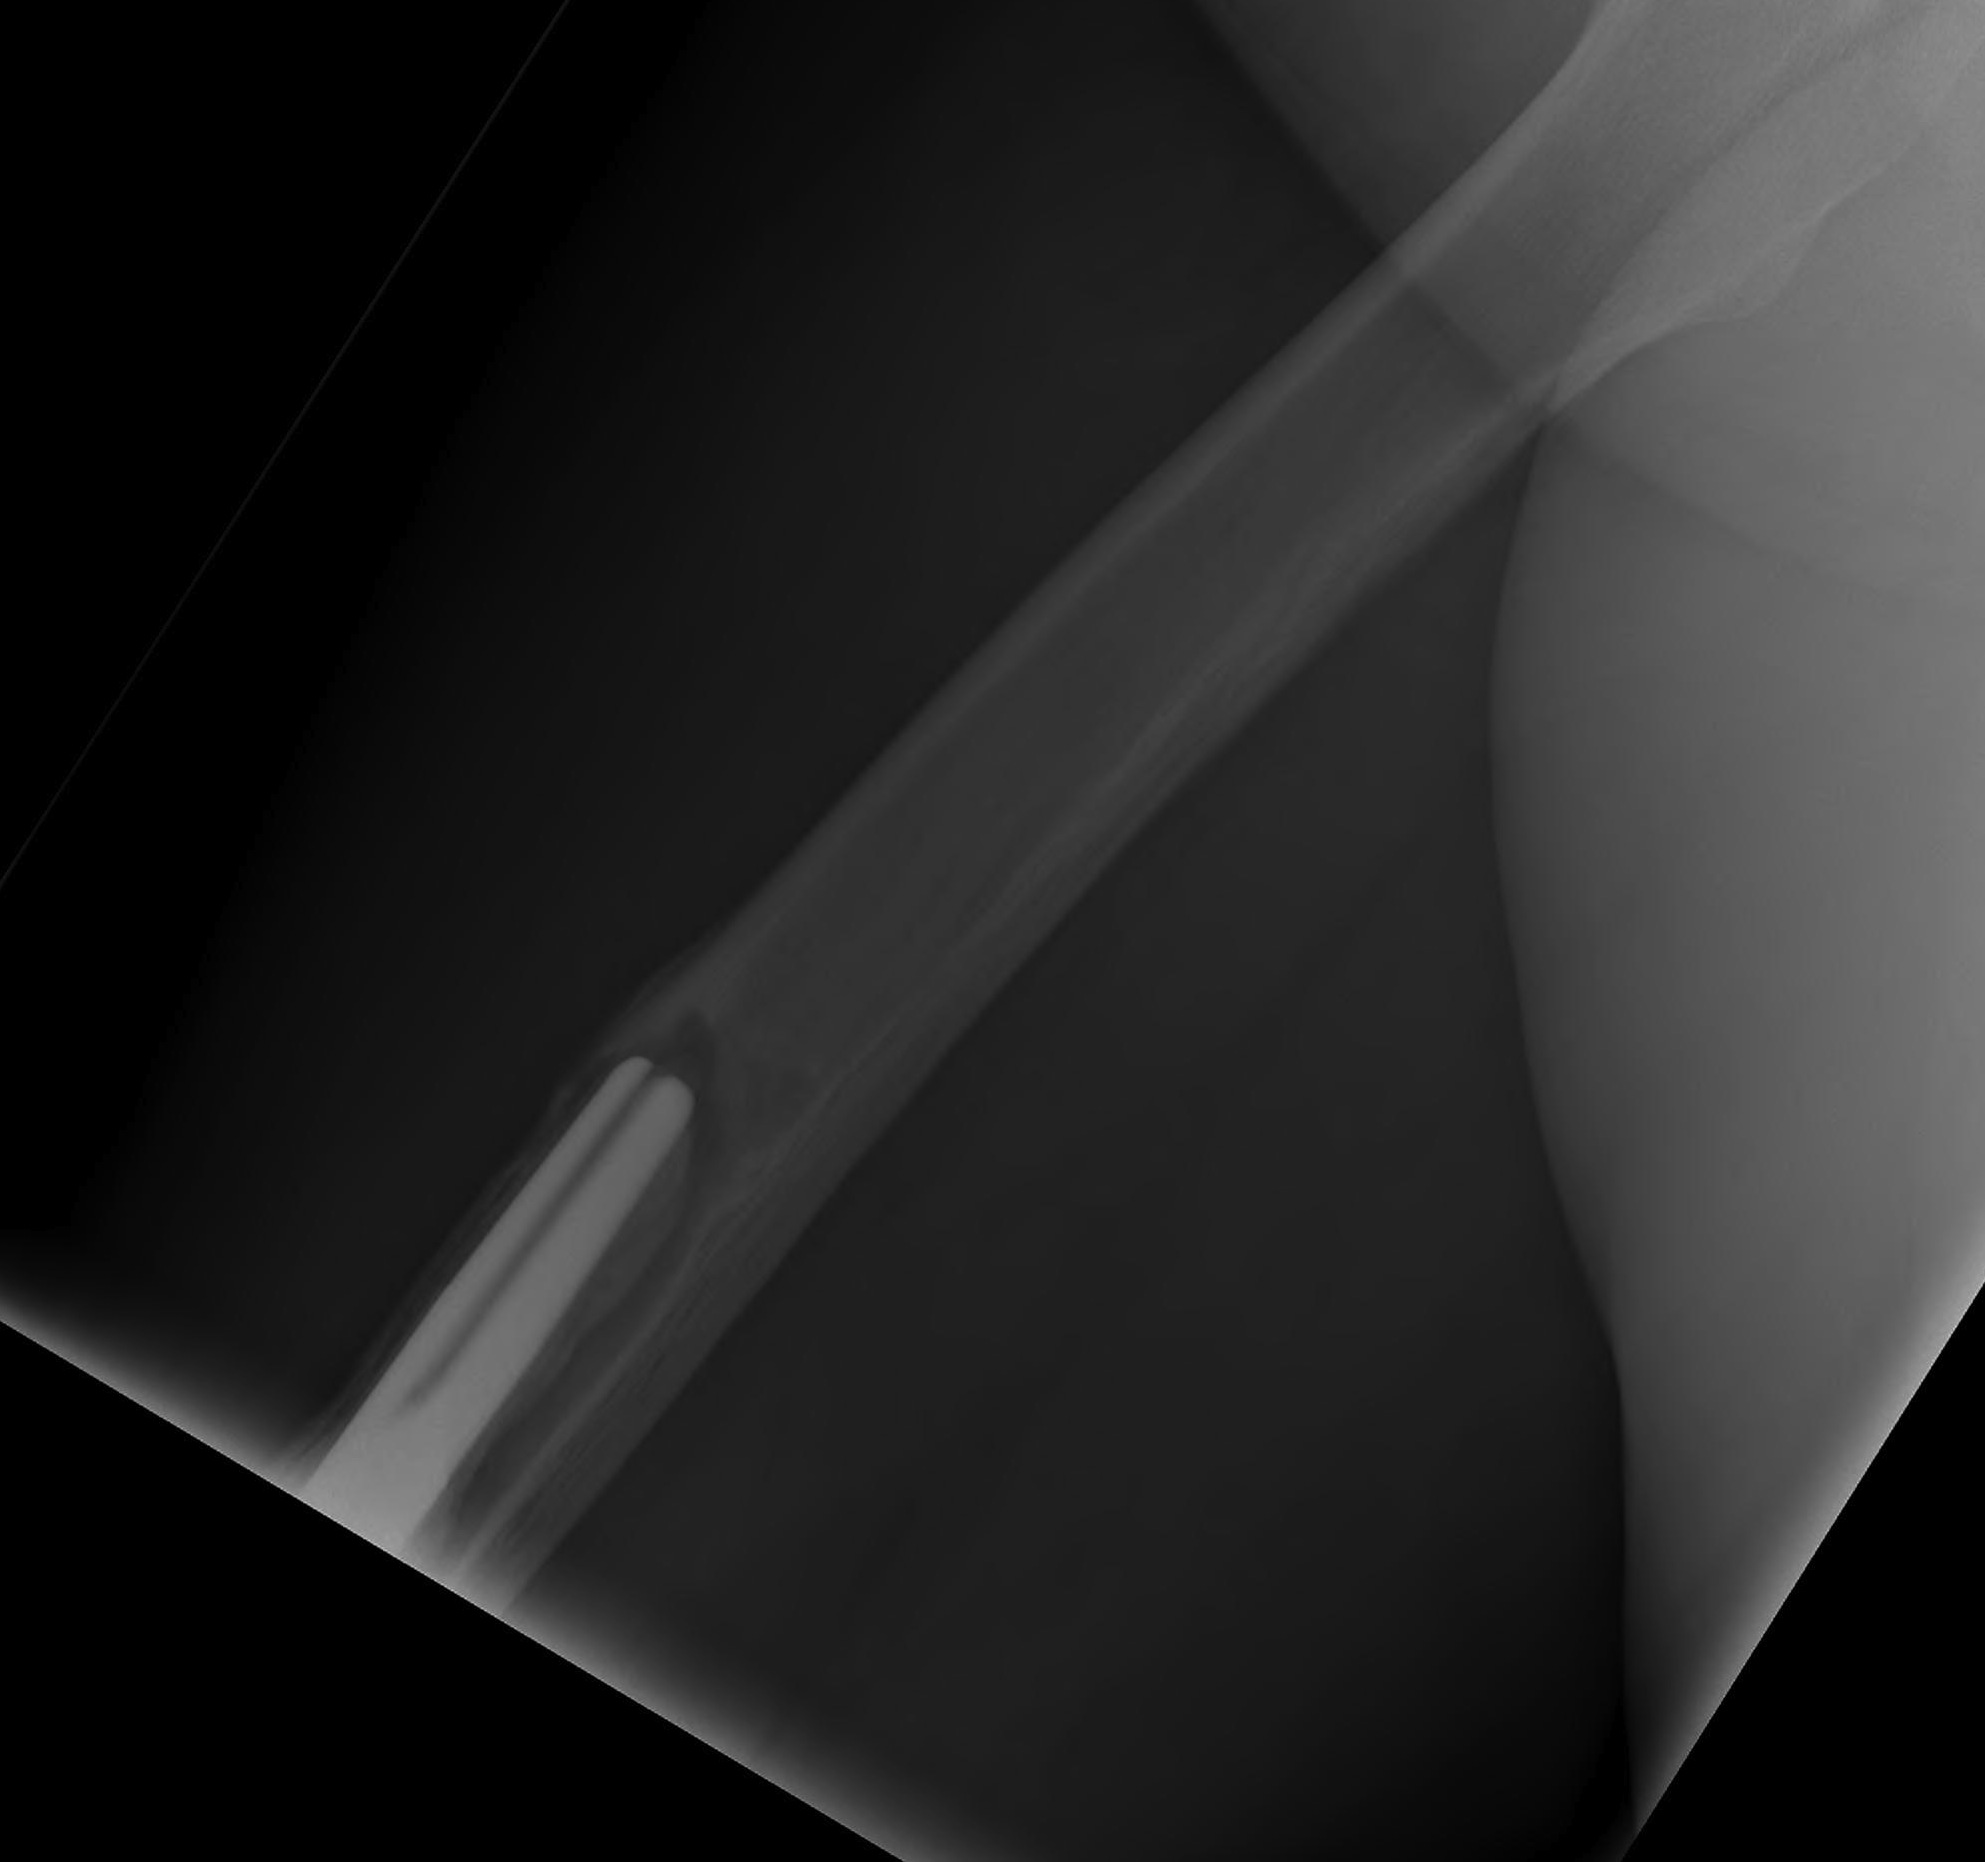

Initial press fit

- implant geometry fits the cortical bone in the proximal femur

- good initial mechanical stability

Biological fixation for success

- good press fit

- minimal micromotion

- bony or fibrous tissue ingrowth or ongrowth